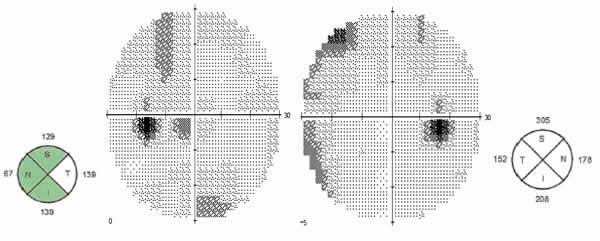

Un varón de 48 años de edad, acudió a Urgencias por una vaga sensación de visión borrosa de ambos ojos de varios días de evolución. Tenía antecedentes de hipercolesterolemia, y era fumador de más 20 cigarrillos al día. El paciente refería haber tenido relaciones heterosexuales de riesgo en los últimos meses. En la exploración ocular, la agudeza visual (AV) mejor corregida del ojo derecho (OD) era de 1,0 y la del ojo izquierdo (OI) 0,9. La exploración del segmento anterior y la tensión ocular fueron normales. No había defecto pupilar aferente relativo ni alteraciones de la percepción cromática en ninguno de los ojos. Funduscópicamente, se observó un edema de papila muy asimétrico con un franco borramiento de todo el contorno papilar del OD, pero únicamente del borde temporal papilar del OI. No se apreciaba vitritis, ni exudados o vasculitis en la retina de ambos ojos. En la campimetría realizada mediante analizador Humphrey 24-2, se observó una disminución de la sensibilidad general en ambos ojos, más acusada en OI (fig. 2). La tomografía coherencia óptica (OCT) mostró un espesor medio de la capa de fibras peripapilar de 210,91 micras en OD (engrosamiento de los 4 cuadrantes), y de 118,59 micras en OI (engrosamiento del cuadrante temporal) (fig. 2).

Fig. 2: Espesores peripapilares de la capa de fibras y campimetrías del ojo izquierdo y derecho en el momento del diagnóstico.

Fig. 4: Normalización de los espesores peripapilares de la capa de fibra y de las campimetrías del ojo izquierdo y derecho a las 4 semanas tras inicio del tratamiento antibioterápico.